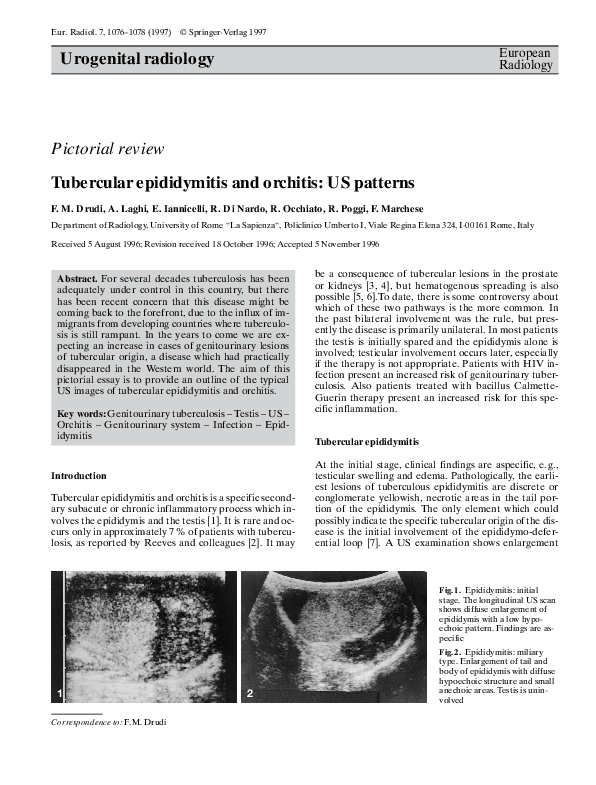

Pdf Tubercular Epididymitis And Orchitis Us Patterns Andrea